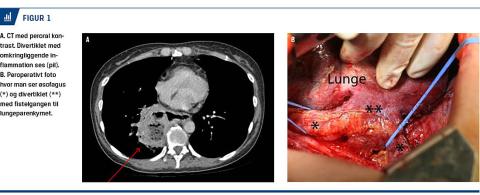

Hun blev genindlagt en uge efter udskrivelse med tiltagende dyspnø, en temperatur på 38,5 °C, stigende infektionstal og trykkende smerter i epigastriet og ryggen. En ny CT af thorax viste progression af væske og inflammation omkring divertiklet (Figur 1A). Patienten blev derfor overflyttet til en specialafdeling, hvor man ved en ny gastroskopi fik mistanke om fisteldannelse til lungeparenkymet. Ved øsofagusskopi med kontrastindhældning i divertiklet under gennemlysning bekræftede man, at der var tale om en øsofagobronkial fistel. Herefter blev der foretaget bronkoskopi, der viste pus i de centrale luftveje fra segment 6 i højre underlap.

Patienten blev efterfølgende septisk, fik respirationsinsufficiens og blev derefter opereret med en højresidig lobektomi af højre underlap samt afstapling af divertiklet i en tværfaglig operation mellem en kirurgisk og en thoraxkirurgisk afdeling (Figur 1B).